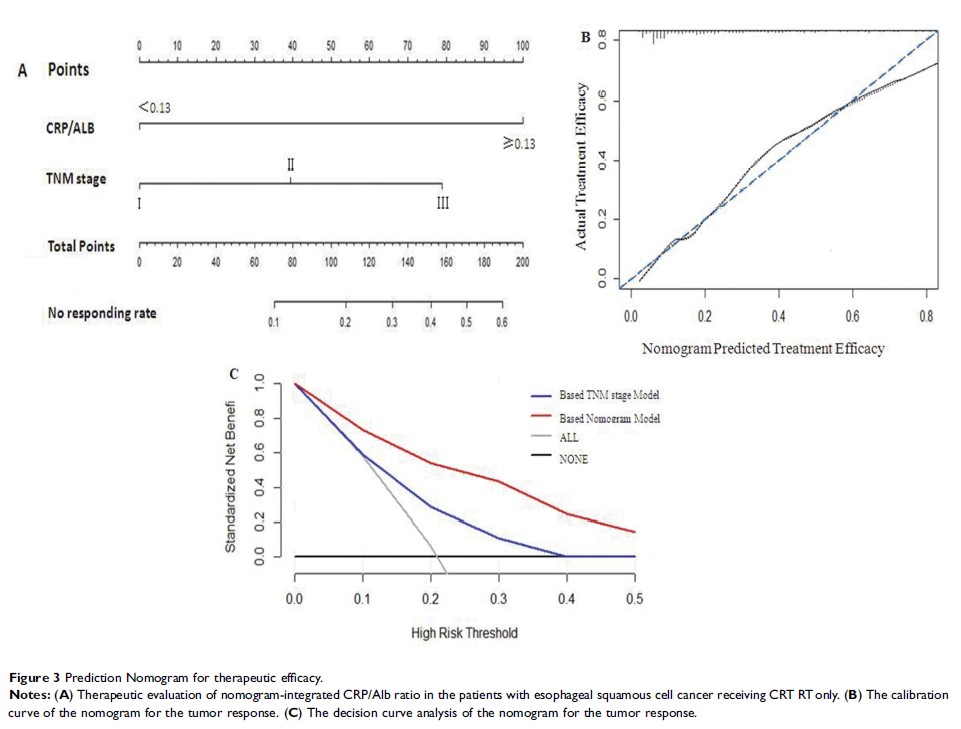

Original Research

诺模图集成的 C 反应蛋白/白蛋白比率可预测接受放化疗的胸段食管鳞状细胞癌患者的疗效和预后

- 作者:Han Zhang, Xin-Wei Guo, Xiao-Xiang Yin, Yang-Chen Liu, Sheng-Jun Ji

- 期刊:Cancer Management and Research